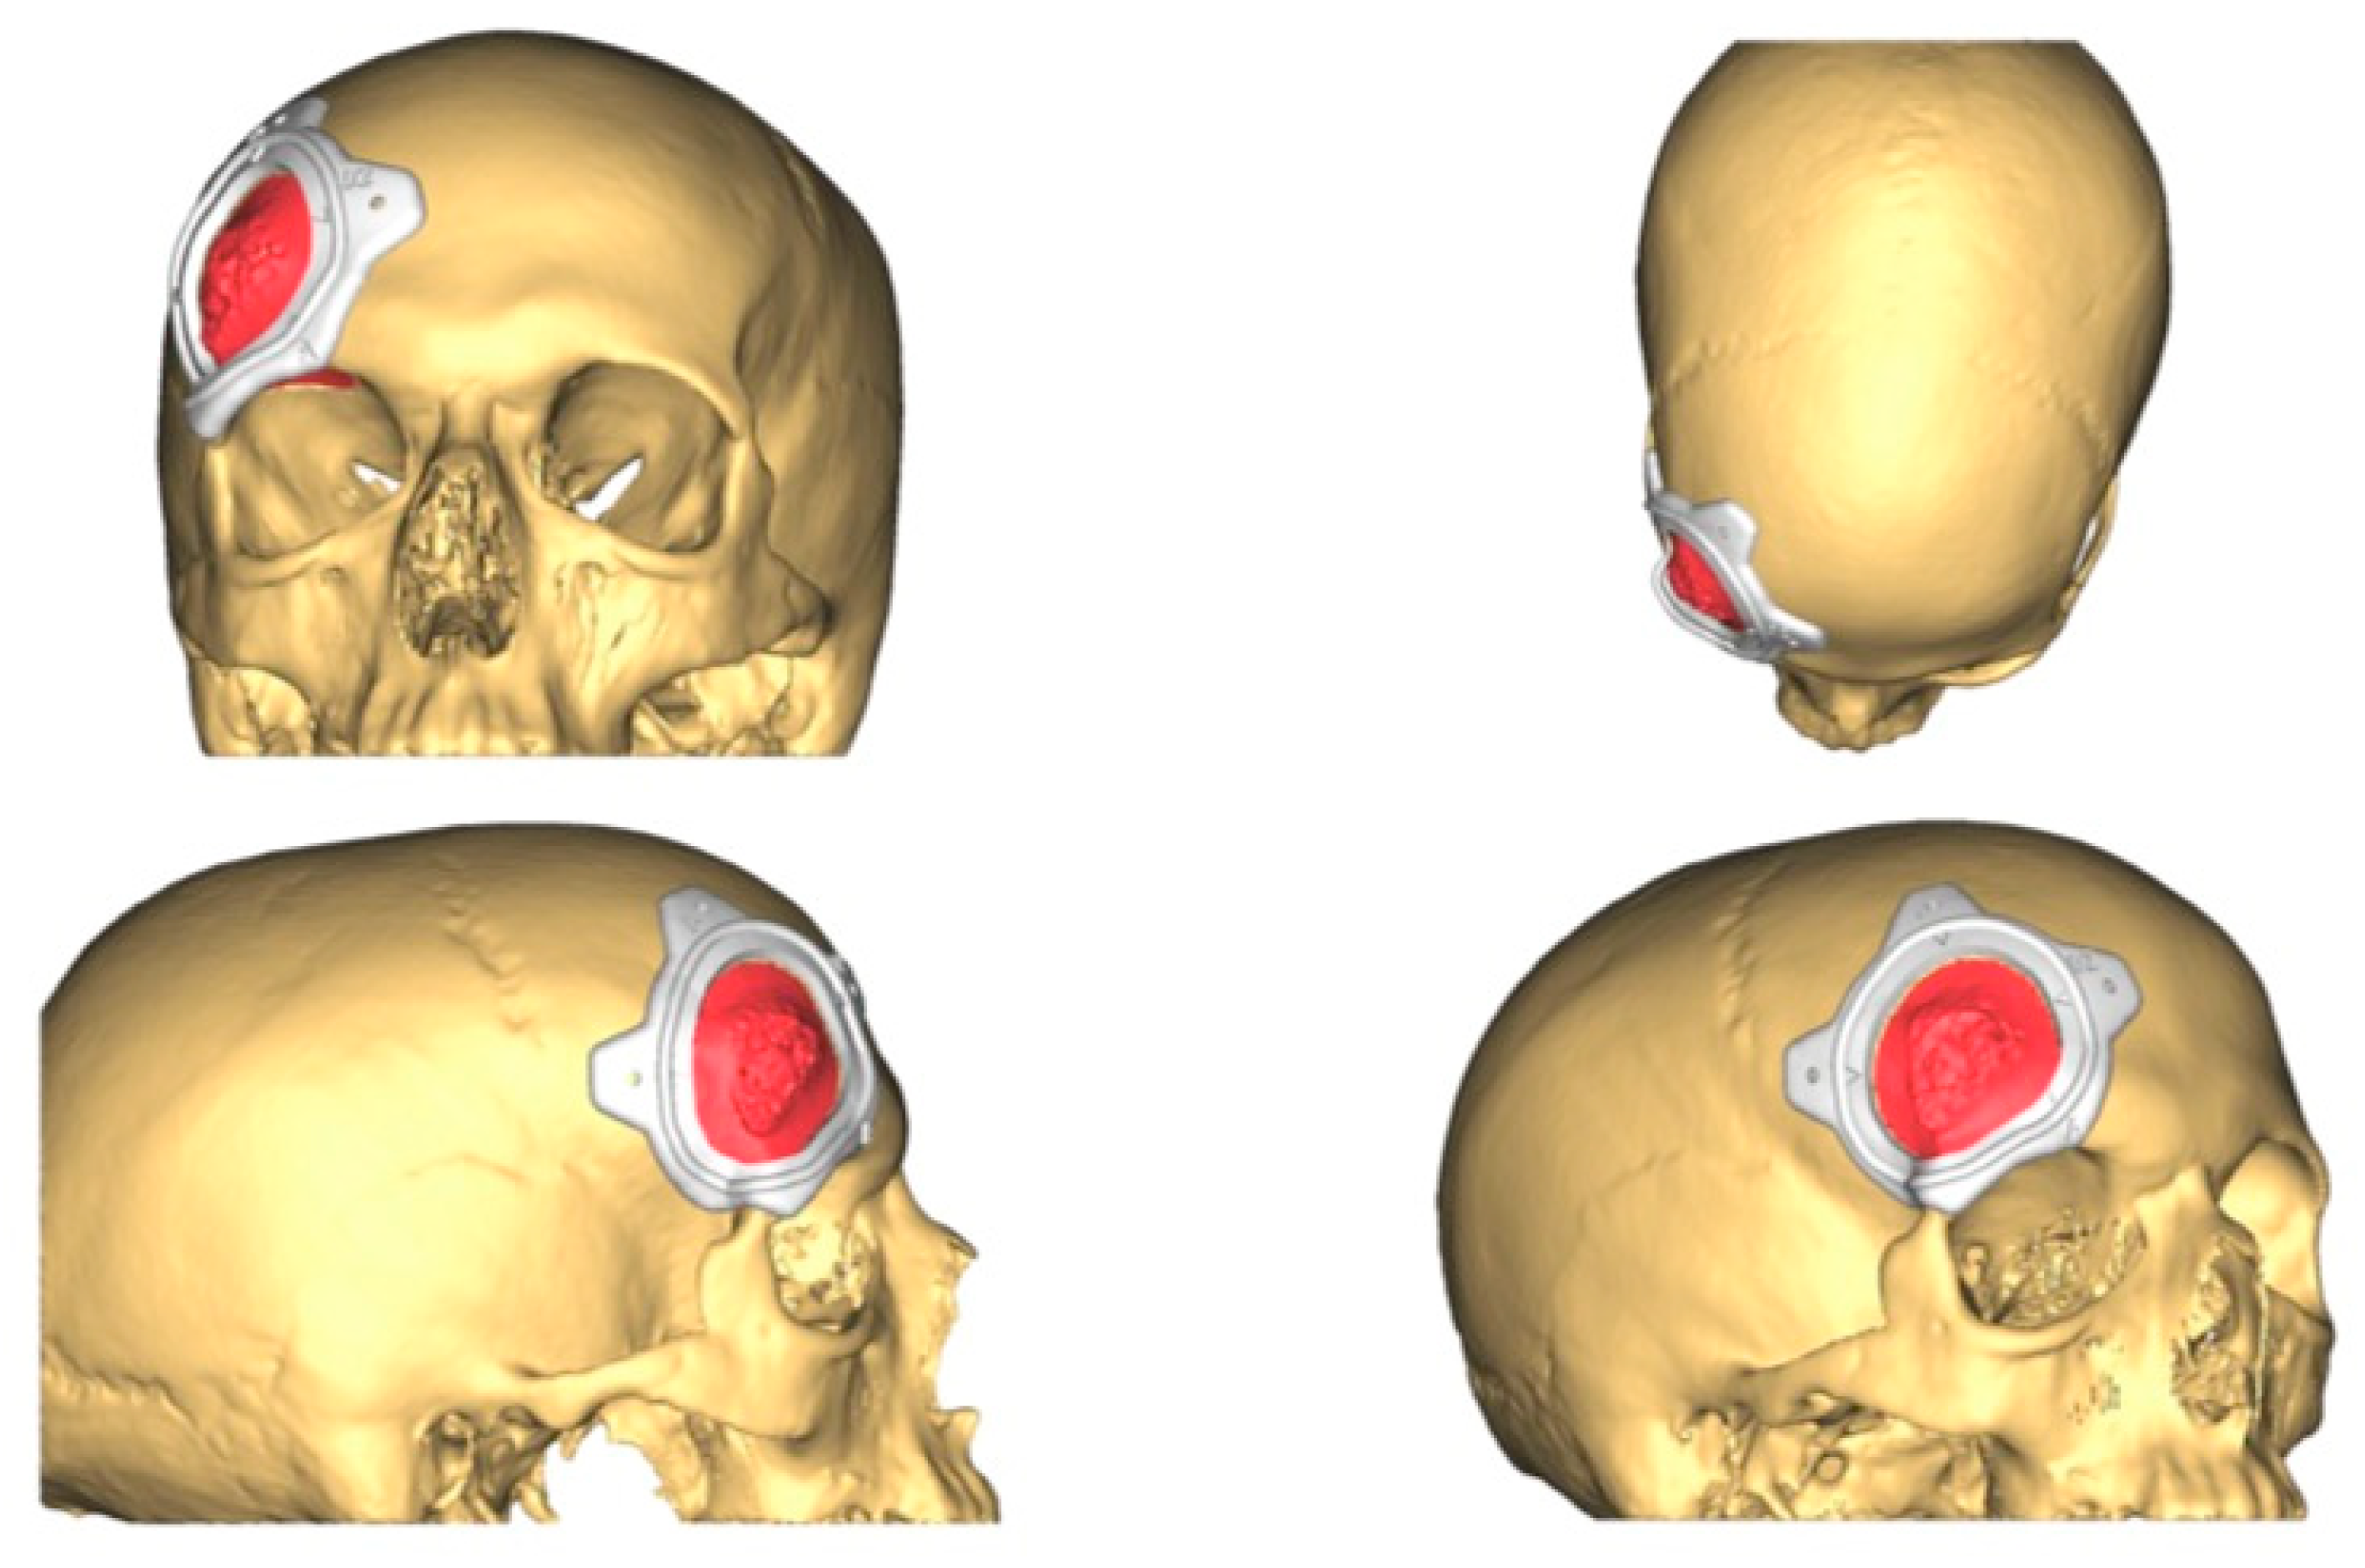

2.3.2. CAD-CAM Design of the PEEK Prosthesis

| 1 | 53/F | L/25 mm | Y | 4 mo | Dystopia | N | CT, MRI | Supraorbital rim, orbital roof | Intraosseous venous malformation | - | Resection + reconstruction | Y | Y | 1st, 2nd, 3rd | Coronal | Y | Piezoelectric device | N | PEEK prosthesis | 7 y/N |

| 2 | 54/F | R/33 mm | Y | 9 y | N | Y | CT, MRI | Frontal bone, orbital roof | Intraosseous venous malformation | - | Resection + reconstruction | Y | Y | 1st, 2nd, 3rd | Coronal | Y | Piezoelectric device | N | PEEK prosthesis | 6 y/N |

| 3 | 36/F | L/19 mm | Y | 6 mo | N | N | CT, MRI | Zygoma | Arteriovenous malformation | - | Resection + reconstruction | Y | Y | 1st, 2nd, 3rd | Transconjunctival + blepharoplasty + maxillary vestibular | Y | Piezoelectric device | N | PEEK prosthesis | 5 y/N |

| 4 | 47/M | L/30 mm | N | 2 y | N | N | CT | Zygoma | Intraosseous venous malformation | - | Resection + reconstruction | Y | Y | 1st, 2nd, 3rd | Transconjunctival + lateral canthotomy + maxillary vestibular | Y | Piezoelectric device | N | PEEK prosthesis | 6 y/N |